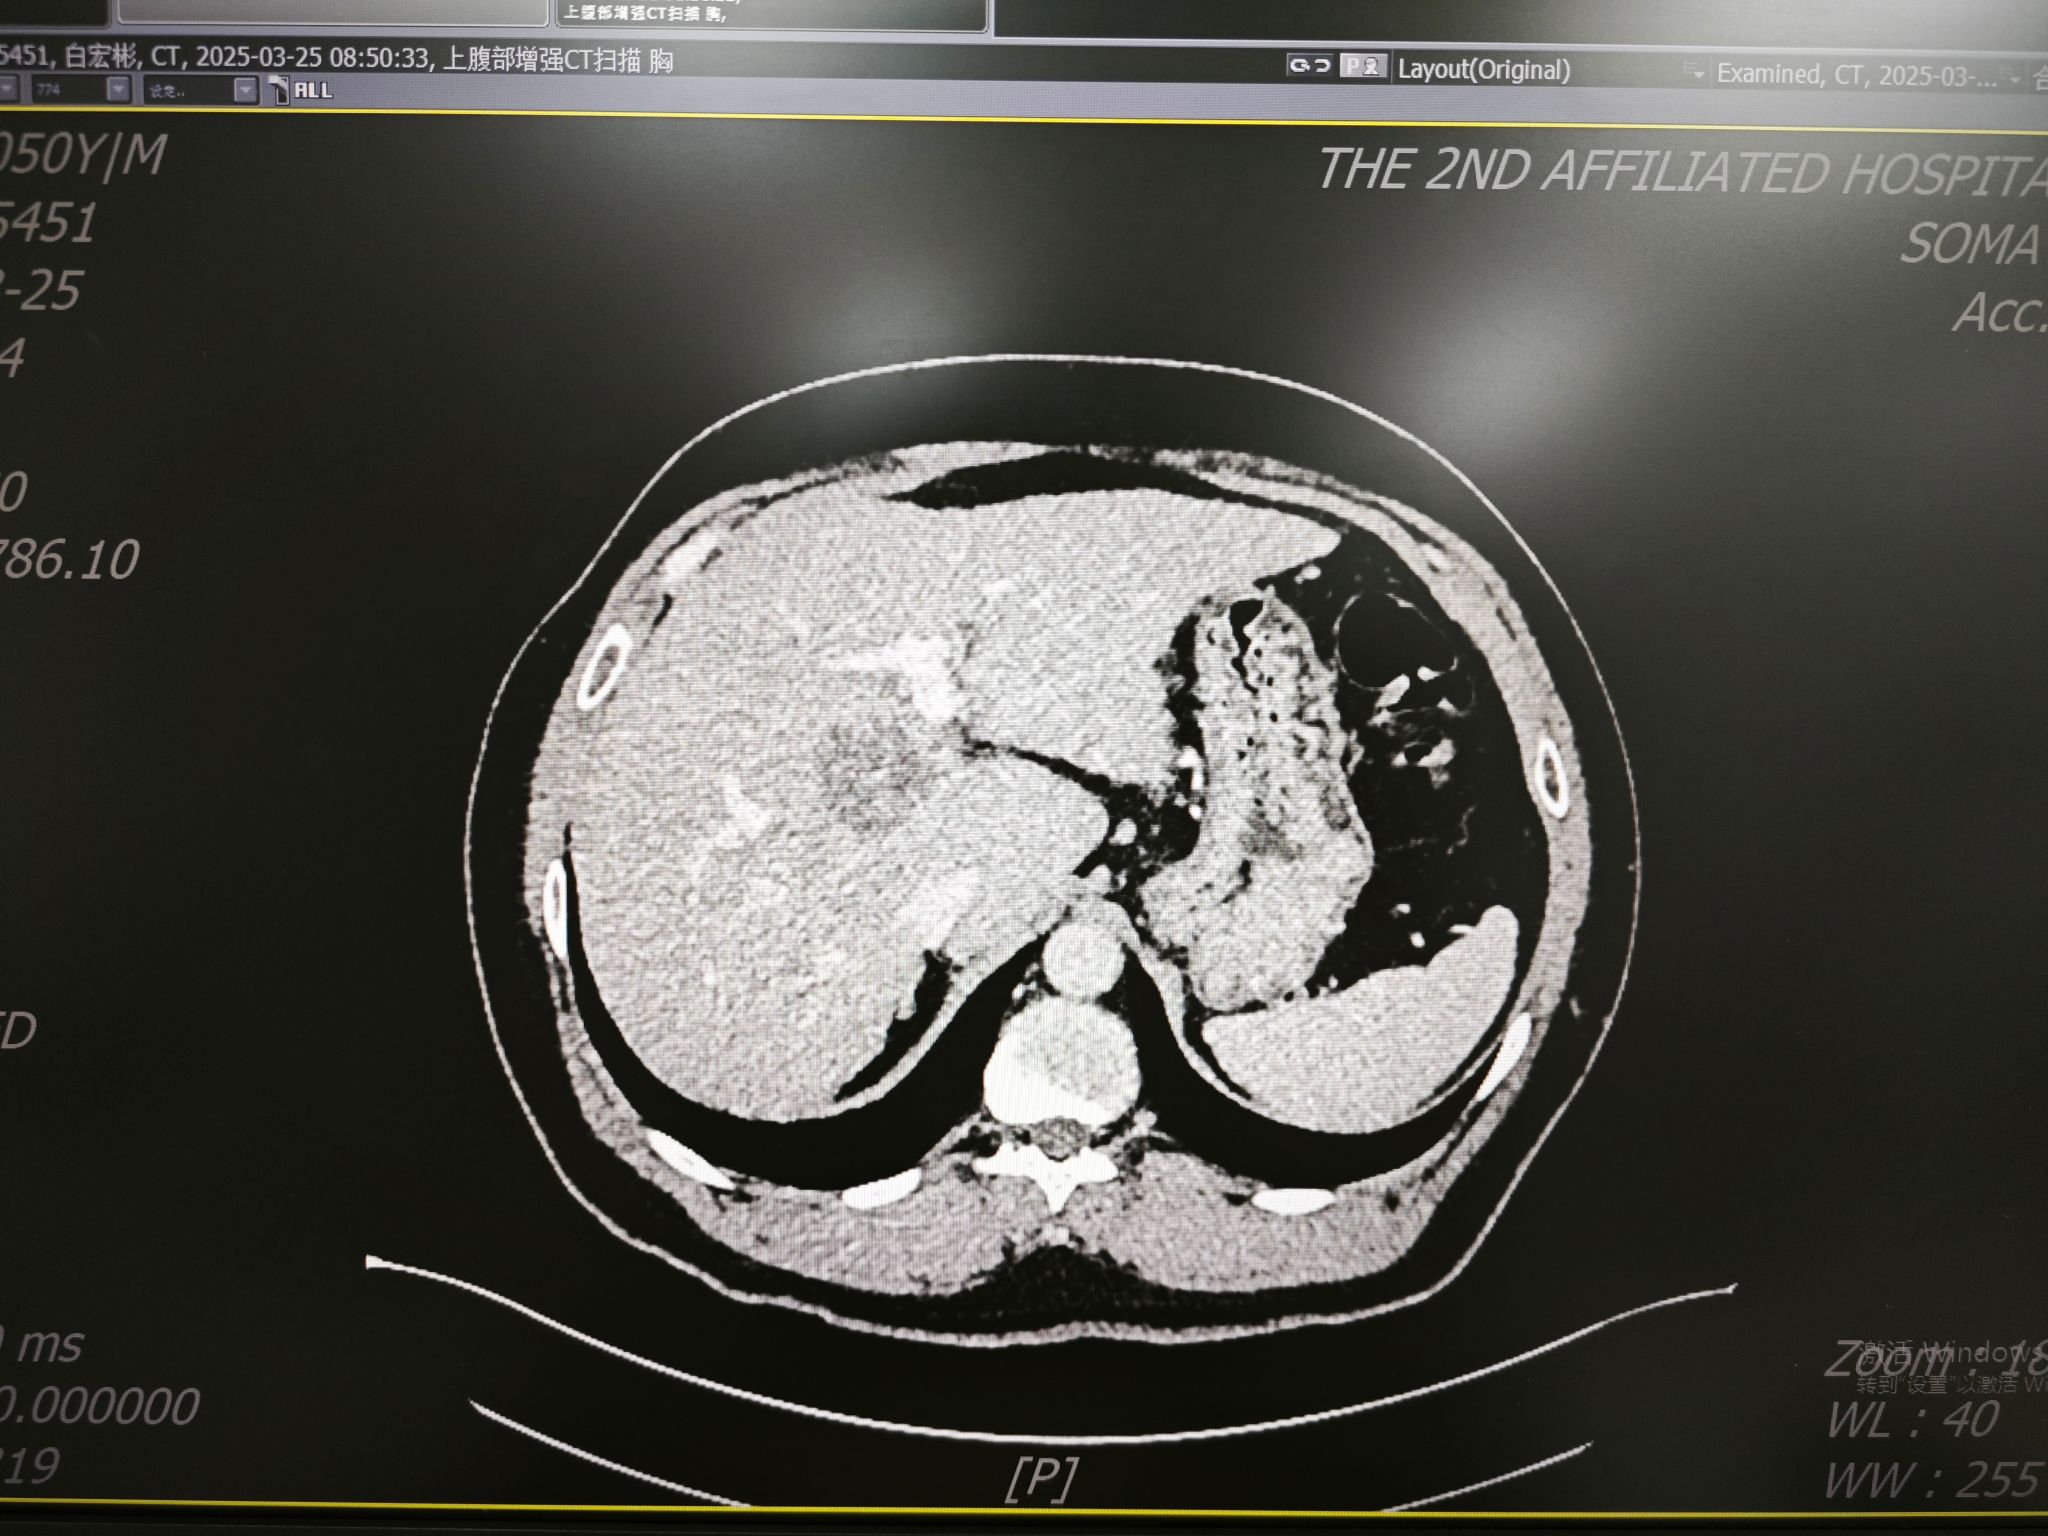

患者白先生,年仅51岁,5年前确诊高血压3级(极高危),长期服药控制;丙肝导致的肝硬化让他的肝脏如风干的枯叶般脆弱;患者因为近期反复发热行腹部CT发现胆囊结石,更致命的是,还有一颗直径4×5cm的肝细胞癌肿瘤,正盘踞在肝尾状叶腔静脉旁的“险要之地”——上方紧贴肝中静脉,后方靠近下腔静脉,左右两侧的门静脉主干紧紧包绕着肿瘤。

“这类患者往往陷入‘两难’:不手术,肿瘤可能迅速进展;若手术,肝功能极可能崩溃。”蒋安教授表示。术前评估显示,患者ICG15分钟滞留率高达30.6%(正常值<10%),意味着手术切除的肝脏不能超过八分之一,否则残余肝脏难以承受手术的创伤。如何在高风险中寻找生机?一场多学科会诊迅速展开。

屏幕上,血管的走向、肿瘤的边界清晰可辨。“肿瘤像一颗嵌在血管网中的‘定时炸弹’。”蒋安教授比喻道。肝胆胰及肝移植外科蒋安教授、曲凯教授、张威教授讨论后决定采用腹腔镜正中入路,劈开肝脏局部切除肿物,最大程度保留肝组织——如同在血管缝隙中“雕刻”肿瘤,既要完整切除病灶,又要保全肝中静脉、门静脉左右支及下腔静脉的完整性。

无影灯下,腹腔镜镜头缓缓探入患者腹腔。高清画面中,肝硬化导致的肝脏表面凹凸不平,肝脏与结肠及网膜粘连严重。蒋安教授先与超声科余珊珊教授合作进行术中超声定位,保证切面位于肿瘤正上方,保留各种管道结构。采用Pringle法行全肝阻断,通过超声刀沿肝正中线逐渐劈开肝组织至肿瘤上方,进而沿着肿瘤边缘精雕细琢,仔细分离各支血管离断进入尾状叶的血管、胆管;麻醉团队实时保障。手术紧张而有序的进行,历时9小时,肿瘤被完整切除,肝中静脉与门静脉完整保留,术中出血量800ml,远低于同类开放手术,肝脏组织得到最大程度的保全。